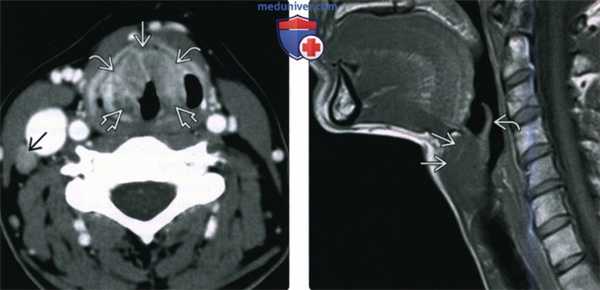

(Слева) При аксиальной КТ с КУ визуализируется небольшое вторичное внутреннее ларингоцеле в краниальных отделах окологортанного пространства слева.

(Справа) При аксиальной КТ с КУ на уровне голосовых связок визуализируется инфильтративное объемное образование (ПКР) левой голосовой связки, накапливающее контраст. При эндоскопическом исследовании было обнаружено распространение опухоли на ложную голосовую складку, лежащую выше. При КТ были выявлены признаки местного объемного воздействия, обусловленного вторичным внутренним ларингоцеле.